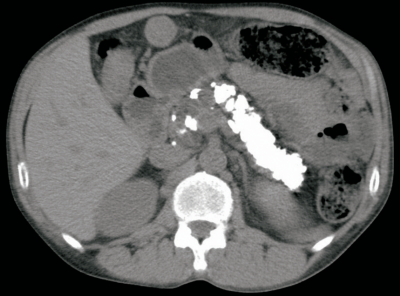

血液所見:赤血球 340万、Hb 12.2 g/dL、Ht 34%、白血球 6,100、血小板 16万。血液生化学所見:総蛋白 6.7 g/dL、アルブミン 3.6 g/dL、総ビリルビン 1.0 mg/dL、AST 74 U/L、ALT 53 U/L、LD 291 U/L(基準 120-245)、ALP 368 U/L(基準 115〜359)、γ-GT 130 U/L(基準 8〜50)、アミラーゼ 44 U/L(基準 37-160)、尿素窒素 14 mg/dL、クレアチニン0.7mg/dL、尿酸 7.9 mg/dL、血糖 278 mg/dL、HbA1c 10.6%(基準 4.6〜6.2)、総コレステロール 209 mg/dL、トリグリセリド 50 mg/dL、Na 140 mEq/L、K 4.0 mEq/L、Cl 103 mEq/L。腹部CTを別に示す。